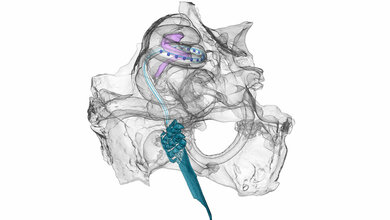

In der Zusammenarbeit von Universitätsmedizin Göttingen (UMG), der Leibniz Universität Hannover (LUH), der Exzellenzcluster Multiscale Bioimaging „Multiscale Bioimaging: Von molekularen Maschinen zu Netzwerken erregbarer Zellen“ (MBExC) und Hearing4all, sowie des Göttinger Start-Up Unternehmens OptoGenTech GmbH und des CI-Herstellers Advanced Bionics GmbH fokussiert das Projektvorhaben nun auf ein Kernstück des optischen Cochlea-Implantats: Für die Elektronik zum Betreiben der Laserdioden soll ein hochintegrierter und verlustleistungsarmer Chip entwickelt und in die Elektronik des optischen CI aufgenommen werden. Das Projekt soll den Weg zur ersten klinischen Prüfung des optischen CI ebnen. Die Beteiligung der beiden Unternehmen sei für das Gelingen des Projekts und dessen spätere wirtschaftliche Verwertung von großer Bedeutung. Der Forschungsansatz erhält eine Förderung in Höhe von rund 0,7 Millionen Euro über das Förderprogramm „Durchbrüche: Unterstützung von Kooperationsprojekten zwischen Wissenschaft und Wirtschaft“ aus Mitteln von zukunft.niedersachsen (früher: Niedersächsisches Vorab).

Geleitet wird das Forschungsvorhaben von Prof. Dr. Tobias Moser, Direktor des Instituts für Auditorische Neurowissenschaften der UMG und Sprecher des Göttinger Exzellenzclusters MBExC, sowie von Prof. Dr.-Ing. Holger Blume, Institut für Mikroelektronische Systeme der LUH und Vorstandsmitglied des Exzellenzclusters Hearing4all am Standort Hannover. Weiter beteiligt ist Prof. Dr.-Ing. Bernhard Wicht, Institut für Mikroelektronische Systeme, Fachgebiet Mixed-Signal-Schaltungen, von der Leibniz Universität Hannover. Das niedersächsische Kooperations-Projekt baut auf umfangreichen Vorarbeiten der Projektpartner, bereits bestehenden CI-Komponenten und einer bereits etablierten Zusammenarbeit auf. Für ihre Pionierarbeiten zur Entwicklung des optischen CI, die das „Hören mit Licht“ durch Kombination eines herkömmlichen, elektrischen CI mit moderner Optogenetik ermöglichen soll, haben Professor Moser und sein Team bereits weltweit Aufmerksamkeit erhalten.

Da Licht räumlich wesentlich besser begrenzt werden kann als elektrische Reize, verspricht die optische Stimulation des Hörnervs die Grenzen der derzeitigen elektrischen CIs zu überwinden. Durch die Kombination eines optischen CI mit einer Gentherapie werde eine fundamentale Verbesserung der Frequenzauflösung erreicht. Dabei werde die Gentherapie genutzt, um einen Licht-aktivierbaren Ionenkanal („molekularer Lichtschalter“) in Spiralganglionneuronen der Cochlea einzuschleusen und diese lichtempfindlich zu machen. Was im Tiermodell bereits erfolgreich umgesetzt wurde, gelte es nun für die Anwendung beim Menschen weiterzuentwickeln.

Bis zum geplanten Start der ersten klinischen Studie im Jahr 2027 bestehe jedoch noch ein erheblicher Forschungsbedarf, so die Projektteilnehmer. So soll mit den Mitteln ein verlustleistungsarmer Chip entwickelt werden, der für das Betreiben der Laserdioden des optischen CIs benötigt wird. Dabei werden die Laserdioden entsprechend der Tonfrequenz aktiviert und das Licht der Dioden über Wellenleiter an die der Tonfrequenz entsprechende Stelle der Hörschnecke geleitet. Das dort ausgekoppelte Licht stimuliert dann die lichtempfindlich gemachten Hörnervenzellen.